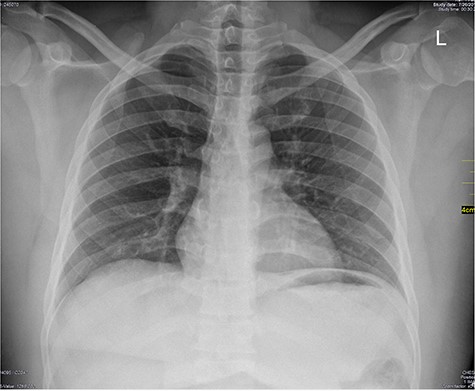

Chest X-ray was normal as shown in Fig. 1. Focused abdominal sonography for trauma (FAST) scan showed mild left perihepatic collection necessitating a thoracoabdominal computerized tomography (CT)-scan which showed external oblique muscle laceration with intermuscular air lucencies and grade 2 hepatic injury as shown in Figs 2–4. Other blood work-up were normal. No other injury was found on secondary survey. His wound was explored under local anaesthesia, primarily repaired, and he was discharged after 24 h of close observation.

Image showing air lucencies in the right intercostal muscles and subcutaneous tissue around the lower right parasternal region.